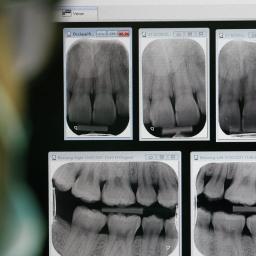

Story Image